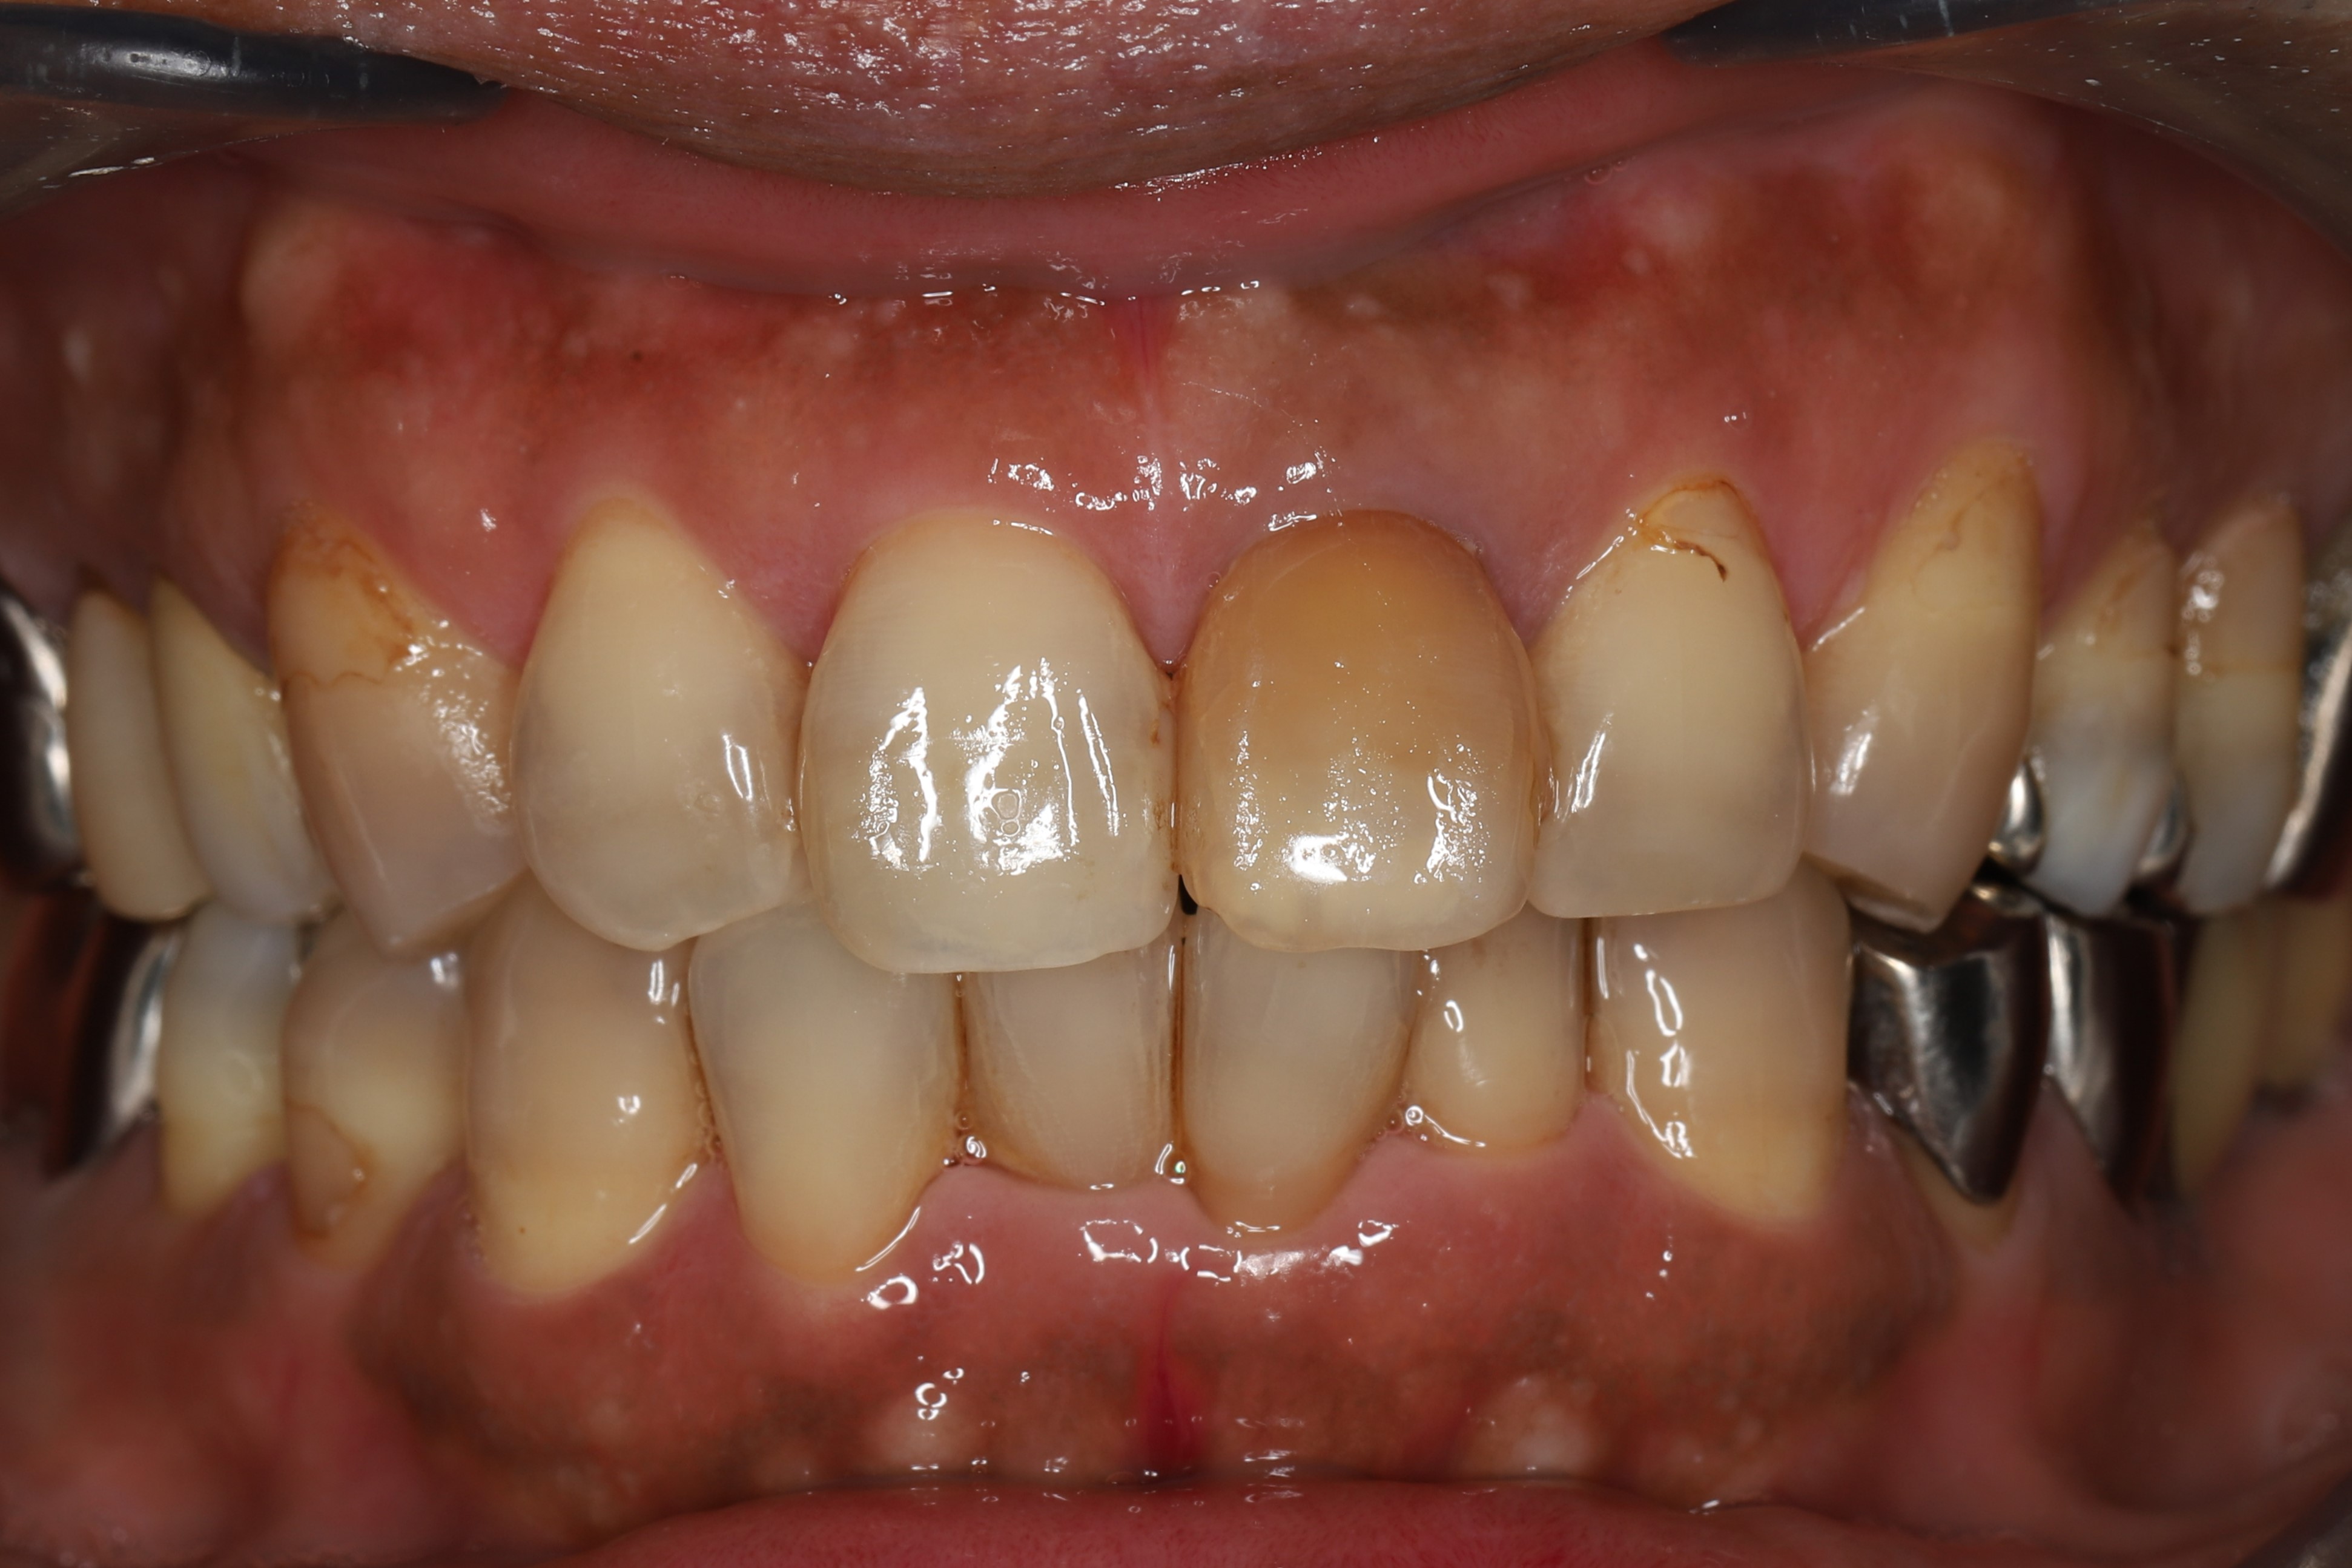

症例1(歯の色にのみ問題がある場合)

治療前

治療後(治療期間2ヶ月)